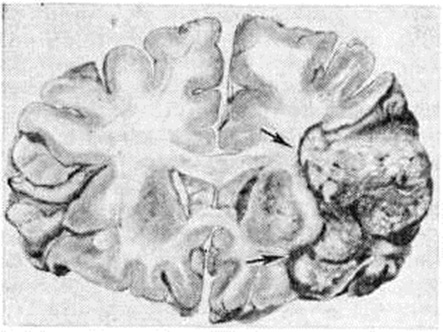

Геморрагический инсульт, как правило, возникает при заболеваниях, протекающих с повышенным артериальное давление. Это обусловлено тем, что сосудистые кризы (смотри полный свод знаний), характерные для гипертонической болезни (смотри полный свод знаний) и артериальной гипертензии (смотри полный свод знаний Гипертензия артериальная), приводят к морфологический изменениям стенок внутримозговых сосудов с нарушением их проницаемости — плазматическому пропитыванию (рисунок 1), некрозам (рисунок 2), образованию микроаневризм (рисунок 3) и их разрывам. Разрыв врождённых артериальных и артериовенозных аневризм может протекать на фоне нормального давления. Преимущественная локализация и характер геморрагий определяются особенностями ангиоархитектоники различных отделов мозга. При гипертонической болезни наиболее тяжёлым изменениям подвергаются сосуды подкорковых узлов и зрительного бугра. Это объясняется отхождением глубоких ветвей под прямым углом от средней мозговой артерии, являющейся продолжением внутренней сонной артерии, и незначительным числом анастомозов сосудов в этой области. В связи с этим на вскрытии кровоизлияния наиболее часто (40%) обнаруживаются в подкорковых узлах с распространением в прилежащее белое вещество (так называемый латеральные кровоизлияния, то есть расположенные латерально от внутренней капсулы, рисунок 4). Второе место по частоте (16%) занимают обширные кровоизлияния, разрушающие подкорковые узлы, внутреннюю капсулу, зрительный бугор (так называемый смешанные кровоизлияния — рисунок 5). Кровоизлияния в зрительный бугор (так называемый медиальные — рисунок 6) составляют 10%, в мозжечок — 6—10%, в мост мозга — 5% от общего числа внутримозговых геморрагий. Кровоизлияния только в белое вещество полушарий мозга встречаются крайне редко. Подразделение полушарных кровоизлияний на латеральные, медиальные и смешанные имеет особое значение в связи с хирургическим лечением геморрагического Инсульт.

Кровоизлияния типа гематомы сопровождаются образованием полости, содержащей жидкую кровь или свёртки крови; они составляют 85% внутримозговых кровоизлияний, наиболее часто развиваются в подкорковых узлах, реже в мозжечке. Основной механизм развития гематомы — разрыв патологически изменённого сосуда (рисунок 7). Формирование гематомы идёт путём раздвигания кровью вещества мозга с перемещением его участков, что возможно благодаря резервным пространствам (желудочки, подпаутинное пространство). Размеры гематомы при этом превышают объем разрушенного кровью вещества, сдавление окружающих отделов незначительно; лишь при кровоизлиянии в мозжечок сдавление вещества мозга весьма существенно в связи с анатомическими особенностями задней черепной ямки (рисунок 8).